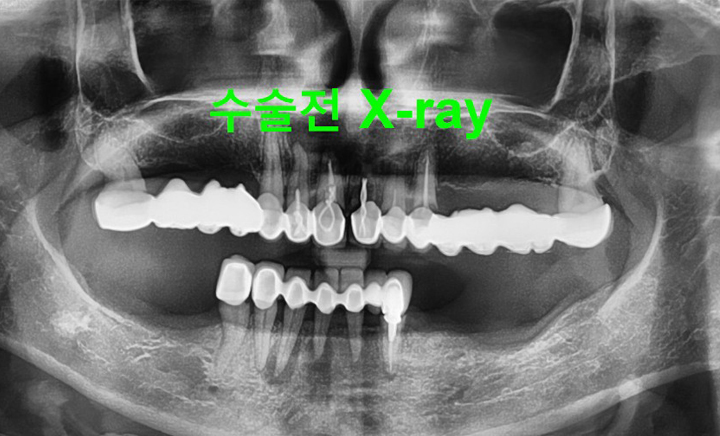

CASE #1